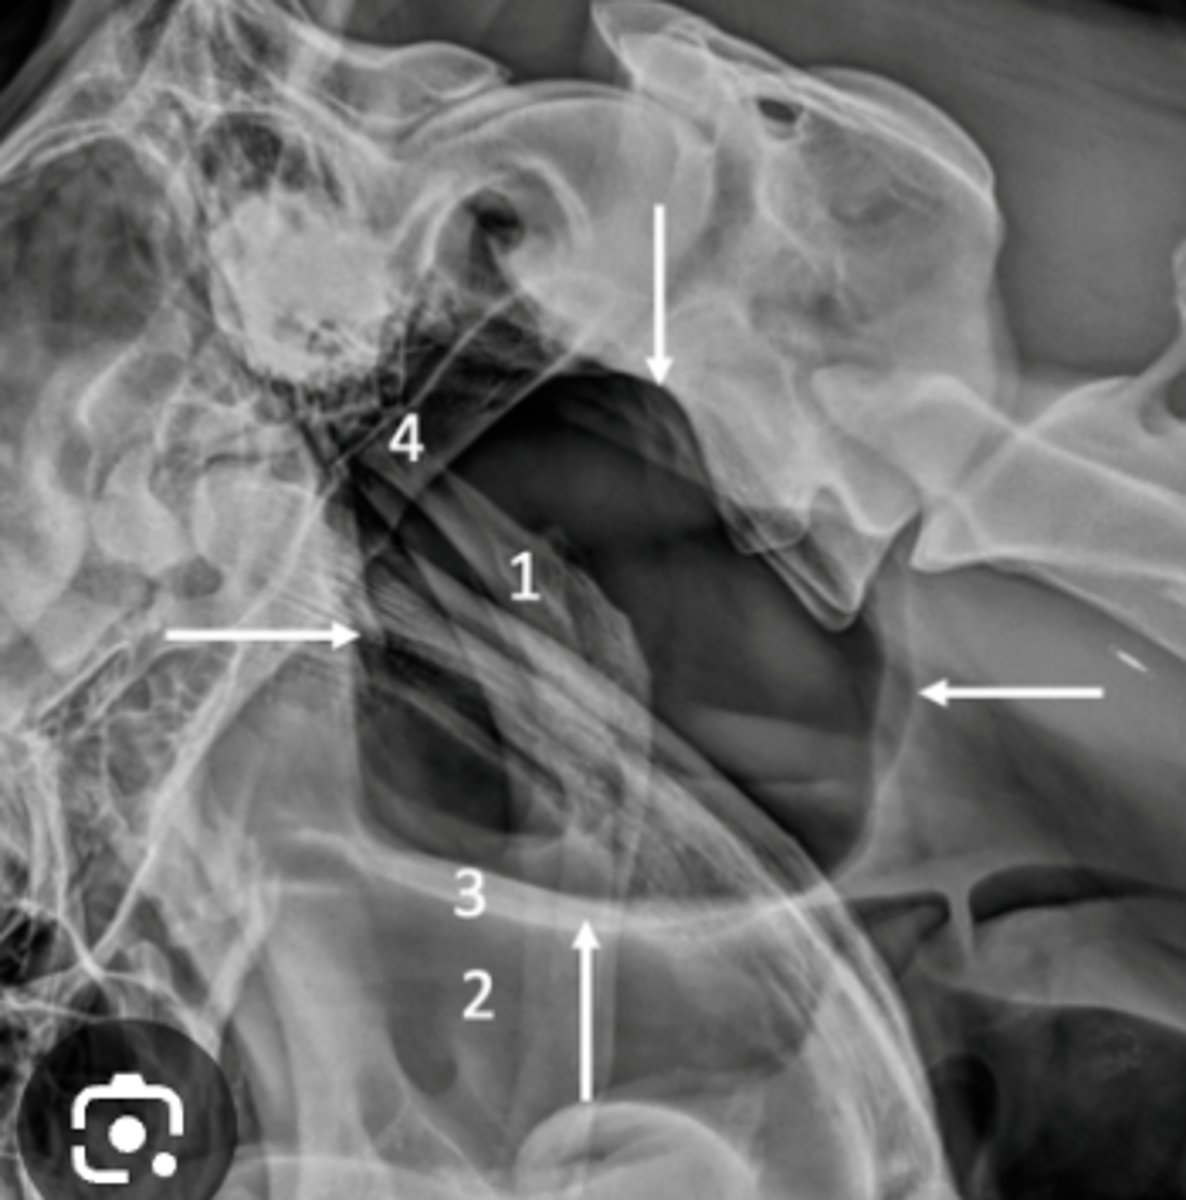

Malalignment

What is wrong with this spine?

Closed intervertebral space

What is seen in IVDD?